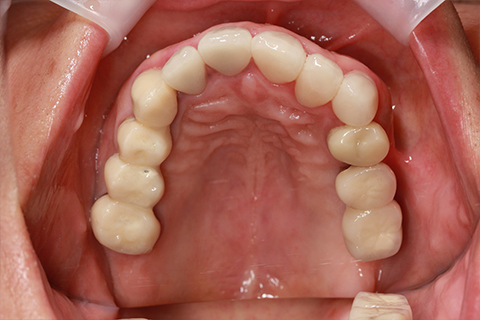

症例3

- 年齢・性別

- 60歳男性

- 治療期間

- 2ヶ月

- 抜歯

- なし

- 治療費

- 66万円

- 備考

- 右下6.7欠損

- 治療内容

- 右下6.7欠損部にインプラント埋入

- 施術の副作用(リスク)

- オペによる知覚障害。インプラントによる歯肉炎。インプラント脱落。